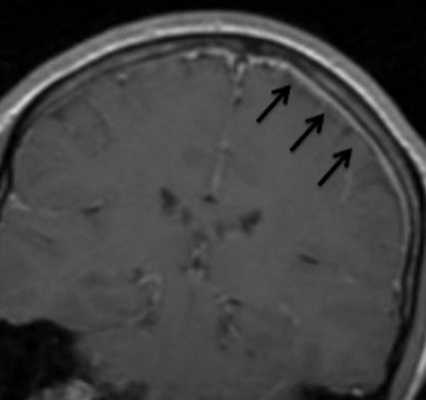

Пневмококковый менингит с миелитом (патологические изменения указаны стрелками)

Рентгенологи проводят расшифровку снимков, исходя из интенсивности сигнала от определенных тканей при применении разных режимов сканирования. МРТ-признаками менингита считают:

- изоинтенсивный ответ от экссудата на Т1 ВИ;

- гиперинтенсивный сигнал от тех же зон на Т2 ВИ;

- признаки гидроцефалии или повышение интенсивности импульсов от борозд и цистерн;

- характерное окрашивание структур, окружающих гнойники, после контрастирования;

- гиперинтенсивный сигнал от абсцессов, визуально заметная капсула;

- сужение просвета артерий или окклюзионные изменения при ангиорежиме сканирования;

- тромбоз вен при магнитно-резонансной венографии.

Подобные отклонения может выявить рентгенолог с практическим опытом и специальными навыками. Обычный человек на МР-снимках увидит только серые и белые пятна. Поэтому при подозрении на менингит больному не стоит самостоятельно назначать томографию и пытаться делать выводы по результатам процедуры. Основными критериями в диагностике патологии считаются клинические проявления и данные лабораторных тестов. Нейровизуализационные методы задействуют в качестве дополнения.